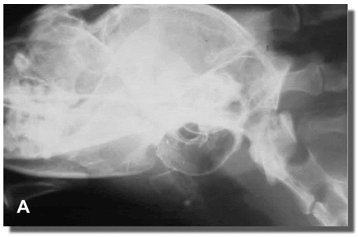

El diagnóstico de las patologías vestibulares periféricas requiere un examen detallado de la faringe y los oídos. La radiología de cráneo en distintas incidencias y la tomografía computada (TC) permiten la correcta evaluación de las ampollas timpánicas y de la porción petrosa del hueso temporal (Figura 8).

Figura 8: Rx de cráneo en incidencia L-L (A), y en incidencia D-V (B) Nótese el aumento de tamaño (expansión) y de la densidad de la ampolla timpánica izquierda. La imagen es altamente compatible con la presencia de pólipos.